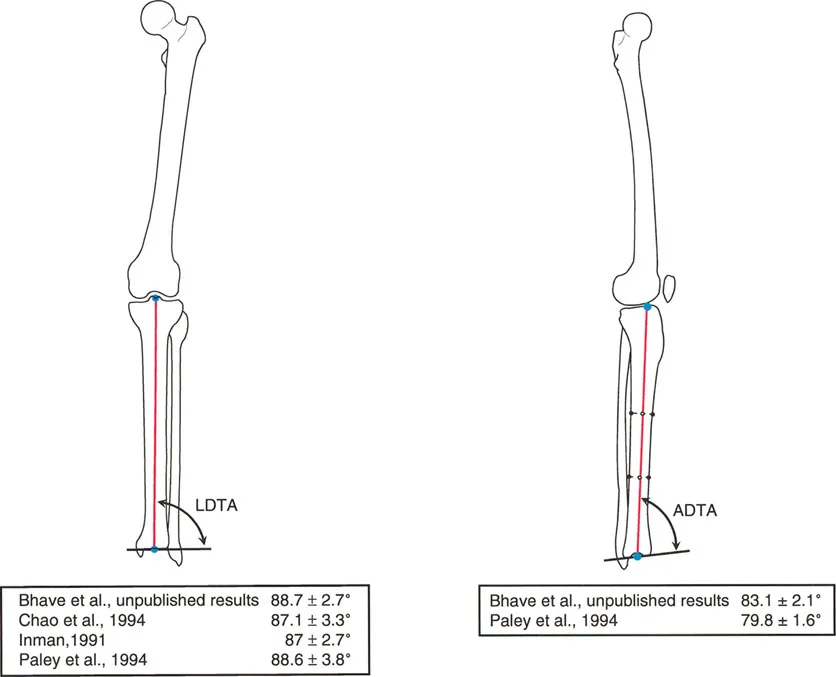

الزاوية الظنبوبية البعيدة الوحشية (LDTA)

هي الزاوية الوحشية (الخارجية) المتكونة بين المحور الميكانيكي لعظم الساق وخط مفصل الساق البعيد (سقف مفصل الكاحل).

* القيمة الطبيعية المقبولة لـ LDTA هي 89 درجة ± 3 درجات.

* ملاحظة سريرية: في الممارسة العملية، نظراً لأن المحورين الميكانيكي والتشريحي لعظم الساق متطابقان تقريباً، فمن الملائم جداً استخدام الخط العمودي على جسم عظم الساق كمرجع لتوجيه مفصل الكاحل.

الزاوية الظنبوبية البعيدة الأمامية (ADTA)

يتم وصف توجيه خط مفصل الكاحل في المستوى السهمي من خلال الميل الأمامي للجزء السفلي من عظم الساق. وهي الزاوية الأمامية المتكونة بين المحور التشريحي لعظم الساق وخط مفصل الكاحل في الصورة الشعاعية الجانبية.

* القيم الطبيعية تتراوح بين 79.8 درجة و 83.1 درجة.

* ملاحظة سريرية: استعادة ADTA أمر بالغ الأهمية أثناء تثبيت كسور الجزء السفلي من عظم الساق (كسور بيلون) لمنع انزلاق عظم الكاحل (Talus) إلى الأمام أو الخلف أثناء المشي.